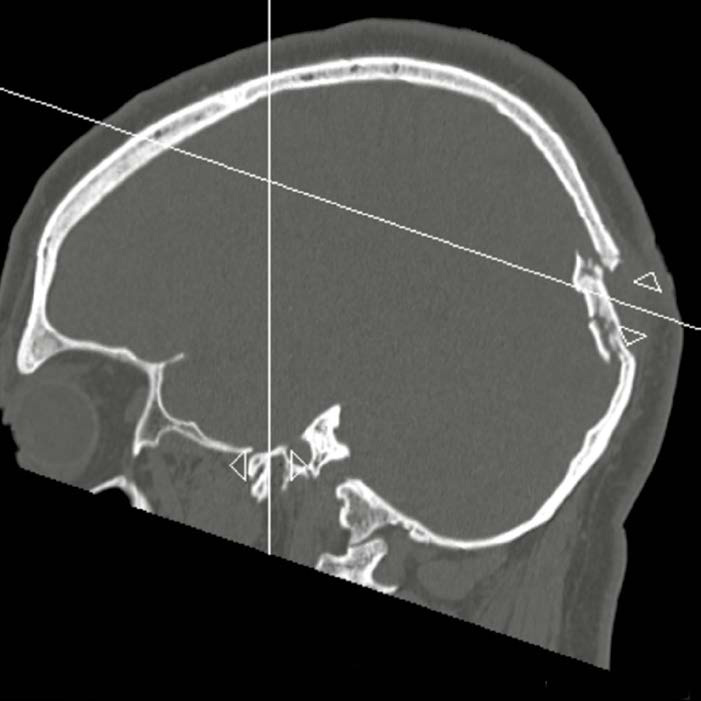

На снимке по МСКТ костей черепа в 3D-реконструкции определяется линейный перелом теменной кости с переходом на височную кость. Линия перелома обозначена стрелками

На снимке по МСКТ костей черепа в 3D-реконструкции определяется линейный перелом теменной кости с переходом на височную кость.